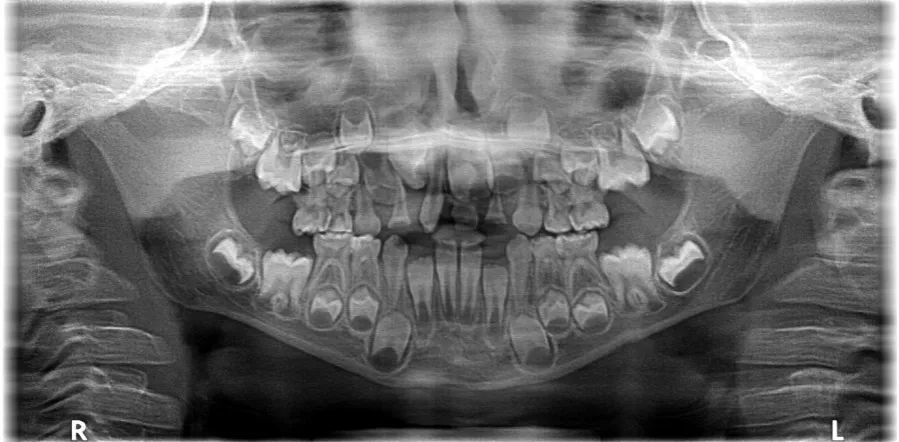

Proces wymiany zębów mlecznych na stałe to fascynujący etap w rozwoju każdego człowieka. Rozpoczyna się on zazwyczaj około 6. roku życia i, nie licząc zębów mądrości, trwa do około 13. roku życia. W tym czasie zęby mleczne stopniowo wypadają, ustępując miejsca większym i trwalszym zębom stałym. Warto podkreślić, że pierwsze zęby trzonowe, tzw. szóstki, są pierwszymi zębami stałymi, które pojawiają się w jamie ustnej wyrzynają się za ostatnimi zębami mlecznymi, nie zastępując żadnego z nich. Są one niezwykle ważne dla prawidłowego rozwoju zgryzu.Ogólna kolejność wyrzynania się głównych grup zębów stałych wygląda następująco:

- Pierwsze zęby trzonowe (szóstki) około 6. roku życia.

- Siekacze centralne i boczne między 6. a 9. rokiem życia.

- Pierwsze zęby przedtrzonowe między 9. a 11. rokiem życia.

- Kły między 10. a 12. rokiem życia.

- Drugie zęby przedtrzonowe między 10. a 12. rokiem życia.

- Drugie zęby trzonowe (siódemki) między 11. a 13. rokiem życia.

- Trzecie zęby trzonowe (zęby mądrości/ósemki) między 17. a 26. rokiem życia, choć ich pojawienie się jest bardzo indywidualne.